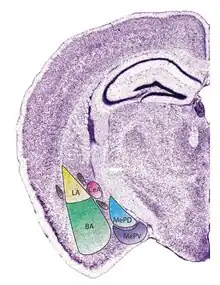

Subdivisions of the amygdala | |

The regions described as amygdala nuclei encompass several structures of the cerebrum with distinct connectional and functional characteristics in humans and other animals.[5] Among these nuclei are the basolateral complex, the cortical nucleus, the medial nucleus, the central nucleus, and the intercalated cell clusters. The basolateral complex can be further subdivided into the lateral, the basal, and the accessory basal nuclei.[3][6][7]